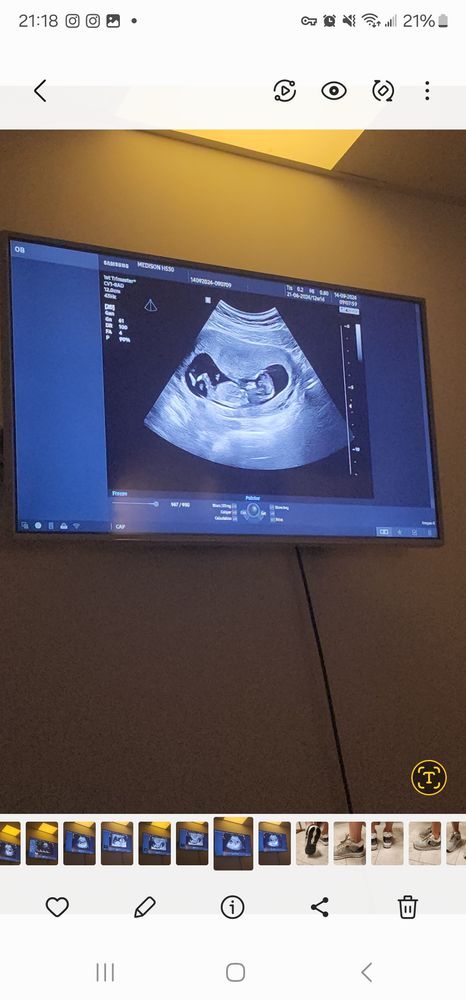

Боялась скрининга, но с дитем все хорошо. Но врач озадачил находкой. Сказал, что у меня неполная перегородка, но это никак не влияет на течение беременности. До этого на узи никаких перегородок не было. Делала и до беременности и в начале, до скрининга узи было в 10,5 недель, там не было перегородки. Он сперва сказал такую фразу, что мол врачи это часто называют гипертонусом, но на самом деле это перегородка. Но я скажу так, перед скринингом я сильно себя накрутила и переживала, что начала болеть поясница и в туалет часто начала бегать маленькими порциями, я так сразу понимаю, что у меня тонус. Фото я прилагаю, может жто все таки тонус а не перегородка....капец просто((((